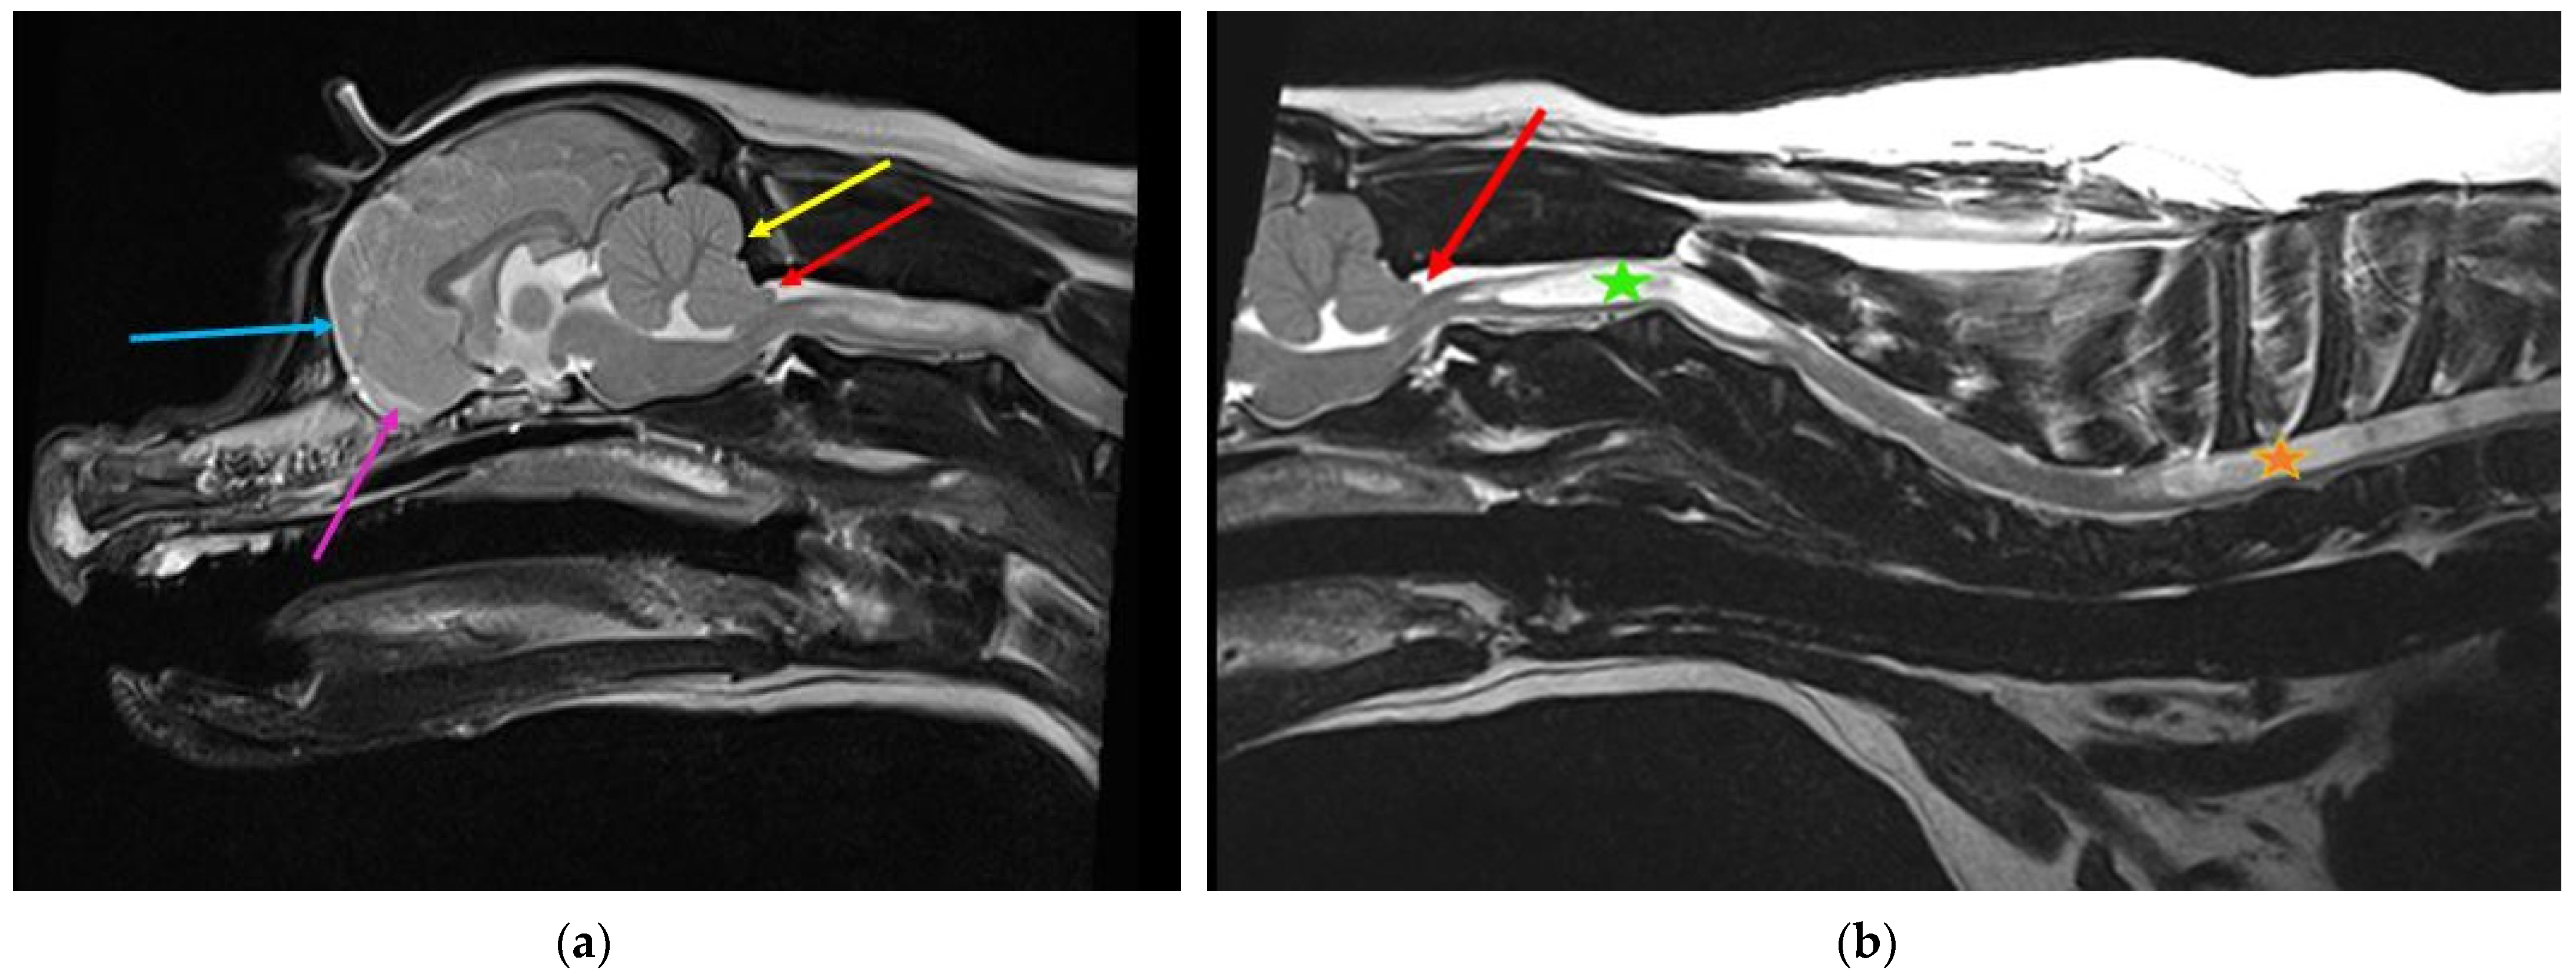

Figure 5.

Two-year-old female Cavalier King Charles spaniel with Chiari-like malformation and syringomyelia. (a) T2-weighted mid-sagittal brain MRI. There is rostrotentorial crowding, giving the rostral forebrain a flattened appearance (blue arrow), with reduced size and ventrally displaced olfactory bulbs (pink arrow). The caudal fossa is reduced rostrally by the displaced forebrain and caudally by a short vertical supraoccipital bone (yellow arrow). The cerebellum is flattened against the supraoccipital bone, resulting in caudal vermal indentation and herniation into or through the foramen magnum (red arrow). (b) T2-weighted mid-sagittal cervicothoracic spinal MRI showing cerebellar vermis herniation (red arrow). There is wide syringomyelia in the cervical (green star) and thoracic (orange star) spinal cord. This dog was presented with signs of pain and fictive scratching (images created by C. Rusbridge and S.P. Knowler).